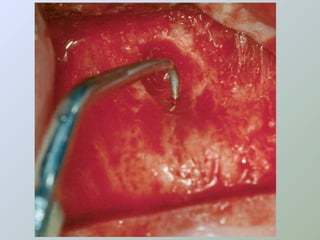

Ressecção do

ápice radicular

- apicectomia -

apicectomia

• Acesso ao canal para

exame e inserção de

material obturador

• Para remover uma porção

não debridada/obturada

da raiz

• Dilacerações radiculares

• Obstruções nos canais

• Acessos às estruturas

linguais/palatinas

• Antes da apicectomia, devemos

expor e isolar o ápice

• Apicectomia com angulação

adequada

• Remover uma quantidade

suficiente para expor canais

colaterais